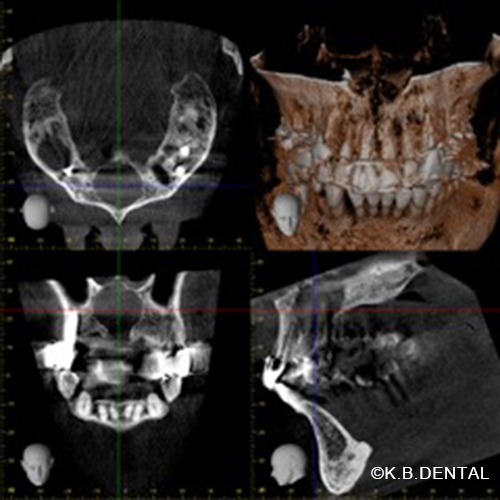

鼻口蓋管嚢胞 症例2

一般的に鼻口蓋管の上皮遺残から生じる先天性嚢胞で、今回は鼻の痛みを主訴に耳鼻咽喉科に受診して判明し摘出手術依頼を受けた症例です。

CT上でも鼻口蓋管を中心に嚢胞様の透過像を認めます

口腔内初見では口蓋に腫脹などは認められません。